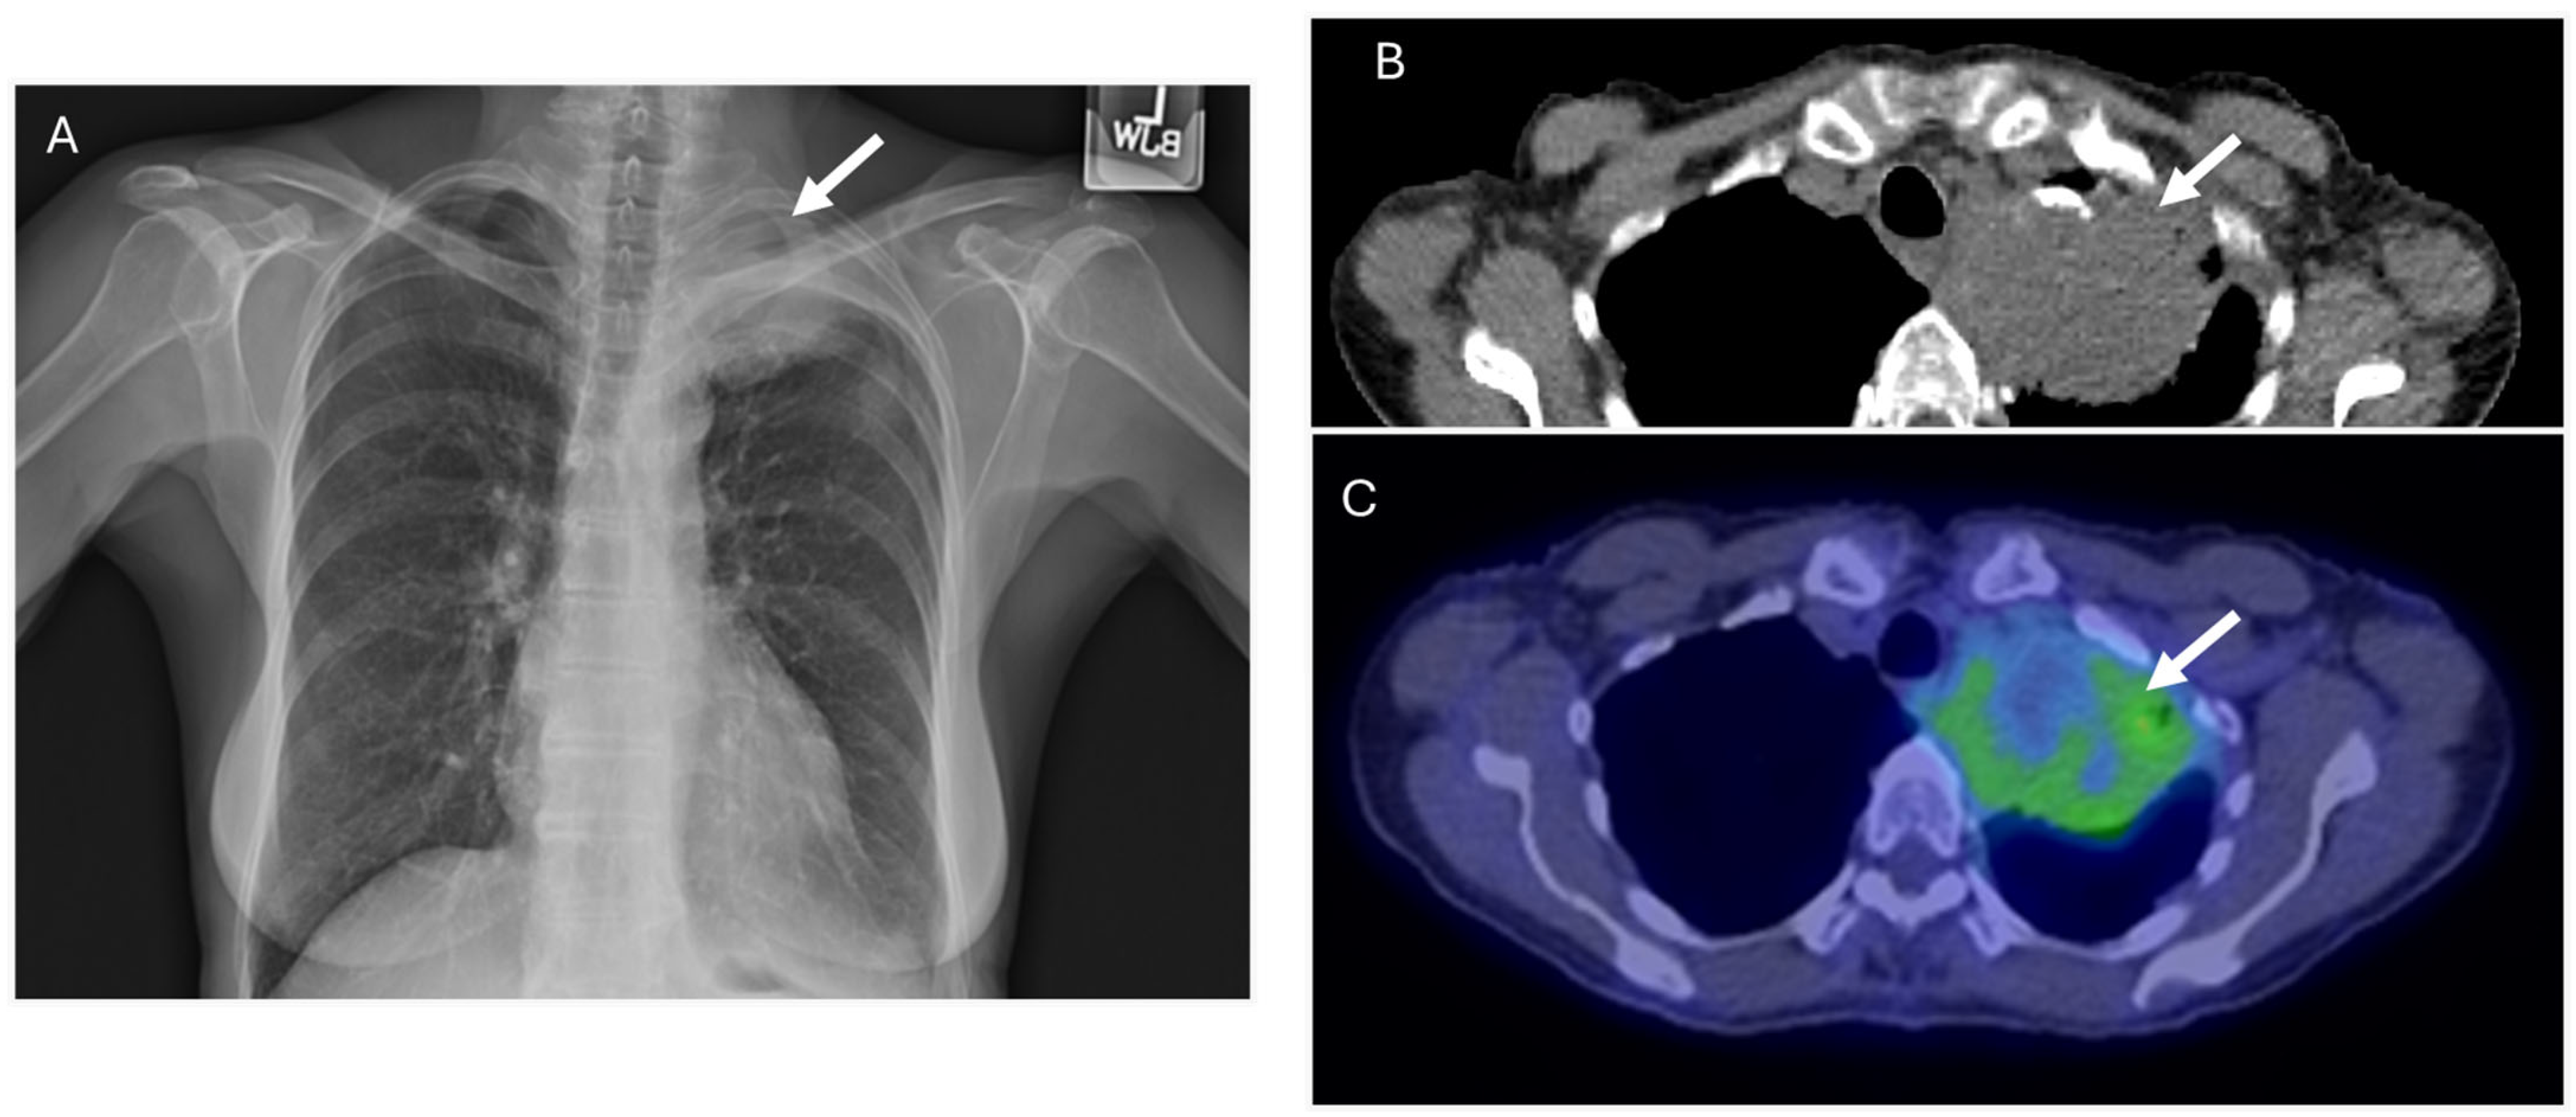

5.1. Type 1 Cryoglobulinemia

6. Imaging Considerations